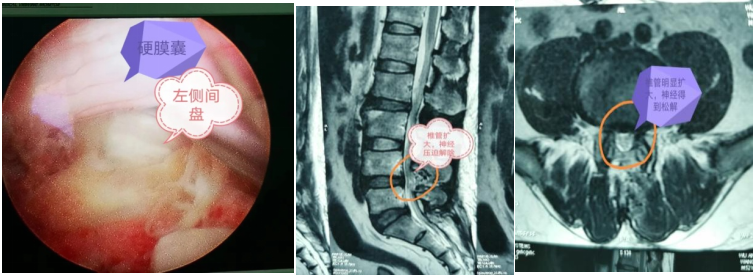

李某及家人多方寻求最佳治疗方法,后从朋友那里得知大竹县人民医院腰椎微创手术可治疗此类疾患,遂来到医院骨科就诊。入院后经过影像学检查显示:“L4/5椎间盘突出(左后方),左侧神经通道狭窄”,诊断其为腰椎间盘突出合并腰椎椎管狭窄。骨科团队对患者病情及年龄特点进行了反复论证后认为:患者虽然比较年轻,但病程较长,病情较重,侧隐窝明显狭窄。考虑到常规开刀手术治疗创伤大、恢复时间长,若采取腰椎椎间孔镜技术,因操作通道窄,侧隐窝可能减压不彻底,不利于神经功能恢复,导致术后症状不能完全缓解。经严谨细致地综合评估、判定,骨科团队决定采用更精准、高效且易操作的“单侧双通道内镜(UBE)下腰椎间盘髓核摘除+腰椎椎管减压术”。

经过充分的术前准备,在麻醉手术室多学科协助下,大竹县人民医院脊柱外科团队凭借过硬的技术实力,顺利为患者完成了手术。术后患者腰部、左下肢疼痛消失,同时左足背伸肌力逐渐恢复,患者及患者家属对治疗效果十分满意。术后第2天李某即可佩戴腰围下床活动,他由衷感叹:“这个手术效果也太好了,恢复速度太快了吧!现在腰腿真轻松!真的太感谢竹医骨科医疗团队了!”